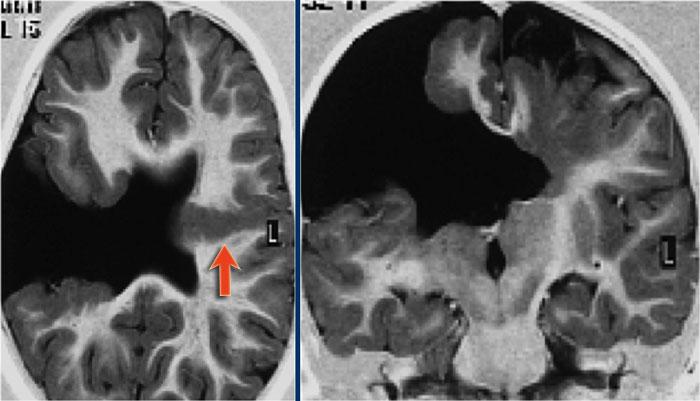

Dấu hiệu xuyên vỏ (Transmantle sign)

Đôi khi vùng tăng tín hiệu được thấy kéo dài từ vùng dưới vỏ đến bờ não thất.

Đây được gọi là dấu hiệu xuyên vỏ (transmantle sign).

Dấu hiệu này phản ánh tình trạng di cư tế bào thần kinh bị gián đoạn.

Hình ảnh của bệnh nhân nam 27 tuổi bị động kinh thùy chẩm kháng trị.

Ảnh FLAIR mặt phẳng coronal và T2W mặt phẳng axial cho thấy dày vỏ não tăng tín hiệu T2 và tăng tín hiệu ở vỏ não và vùng dưới vỏ.

Lưu ý vùng tăng tín hiệu dưới vỏ kéo dài đến não thất bên phải, biểu hiện dấu hiệu xuyên vỏ (mũi tên xanh).

Dấu hiệu xuyên vỏ (transmantle sign) ghi nhận ở một bệnh nhân khác bị loạn sản vỏ não khu trú.